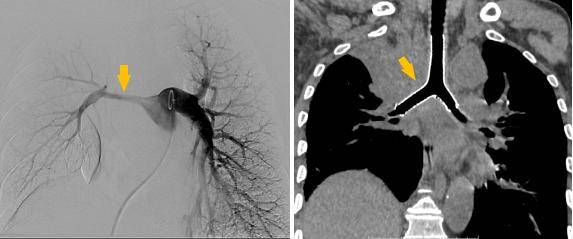

手术过程

潍坊市第二人民医院完成首例气管支架、肺动脉覆膜支架同期植入术